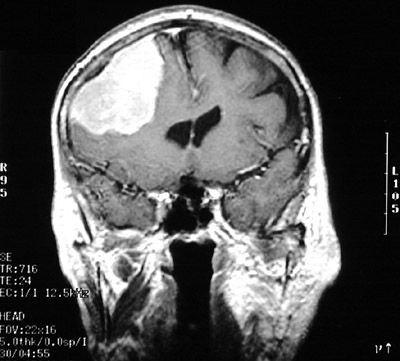

| This MRI scan in coronal views above and below demonstrates bright enhancement of a meningioma in the parasagittal region over frontal lobe. This patient only had headaches. Meningiomas grow slowly and are rarely associated with herniation. In the view below there is tailing of the meningioma into adjacent dura. |